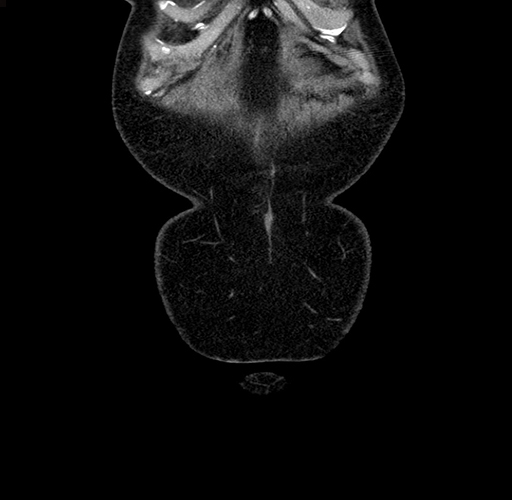

MRI T1